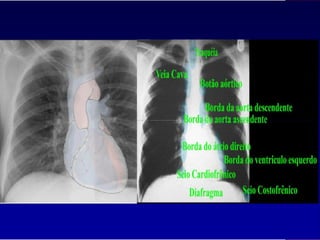

Fisioterapia cardiovascular